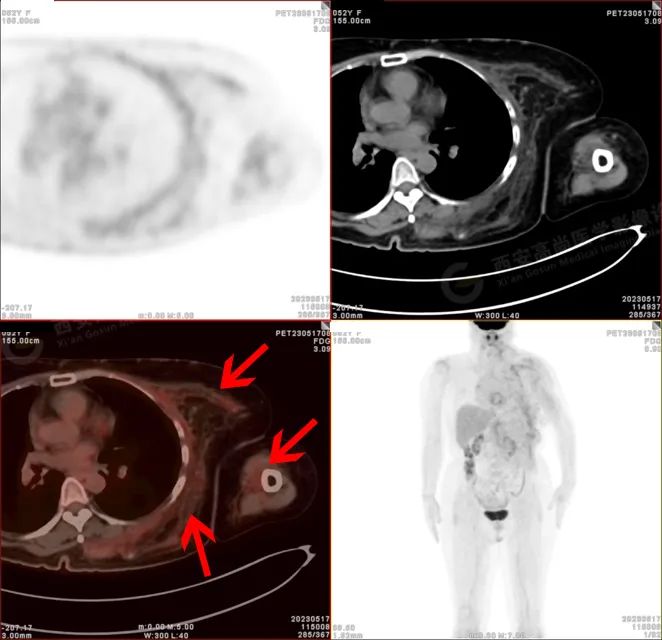

PET/CT 影像图

左侧上臂、颈 4-腰 4 椎体水平左侧颈、左侧肩部、左侧腋窝、左侧胸部(含左侧乳腺)、左侧腹部、左侧背部广泛区域皮下及肌肉区可见疏松、肿胀混杂密度软组织病变,边界模糊不清,相邻骨质结构完整,上述病变呈不均匀放射性摄取轻度异常增高,SUV 最大值介于 1.2-2.4。上述改变,符合韧带样纤维瘤病。